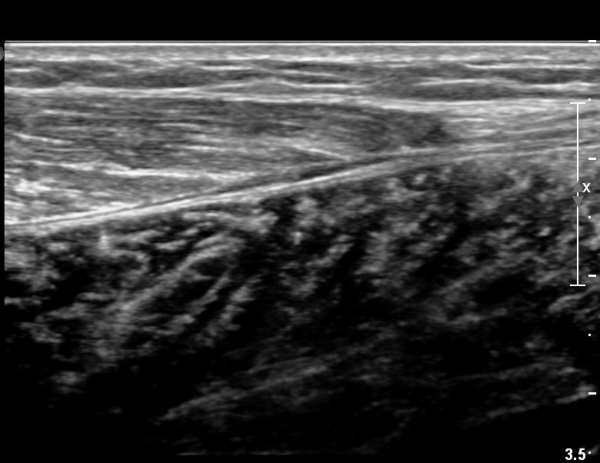

[¹ß¸ñ] simultaneosus tear of GCM and achiles tendon

abrupt leg pain developed during foot volleyball

he walk with severe limping with no weight bearing on rt. leg. on examination, there is local tendernes at GCM and achiles tendon, severe pain with ankle dorsiflexion.

ÃÊÀ½ÆÄ °Ë»ç

rec) short leg splint with crutch gait. he refused splint, then visit other hospital and took operation.